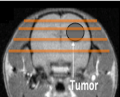

Soigner des cancers avec des minifaisceaux de protons

Une récente étude montre des résultats encourageants sur le traitement de tumeurs radiorésistantes par mini-faisceaux de protons. De précédents travaux avaient déjà prouvé que cette nouvelle méthode préservait mieux les tissus sains que les méthodes plus traditionnelles. Ces travaux ont été menés au laboratoire Imagerie et modélisation en neurobiologie et cancérologie et sont publiés dans la revue Nature Scientific Reports.